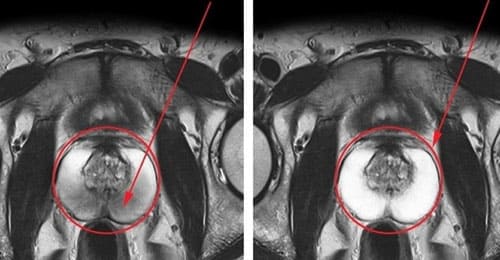

ErexBlue Max se bori proti vnetju prostate:

Pred

Po